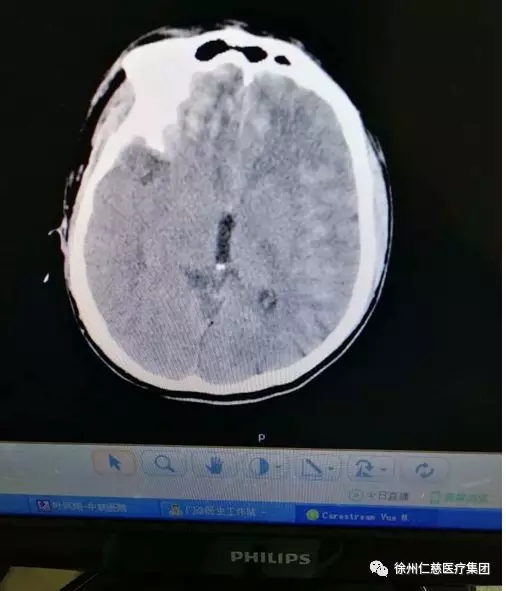

很快CT就做好了,脑出血!

从CT片上可以看到病人右侧额颞部硬膜下血肿、额顶部硬膜外血肿、蛛网膜下腔出血、还有两额顶叶多发脑挫裂伤........于是病人转到脑外科,由脑外科医生接着处理。